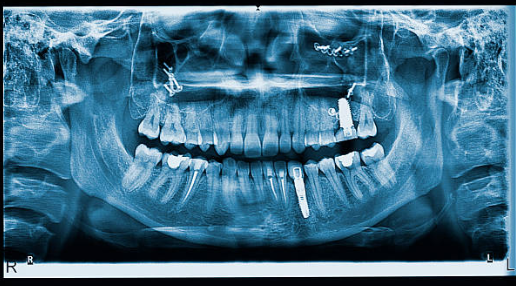

1. 정밀 구강검사 진행

정밀 구강검사 진행은 파노라마 X-ray, 3D CT 촬영 등을 통하여 실시합니다. 정밀한 검사를 통하여 본인에게 정확히 필요한 임플란트 종류 및 개수를 정하며, 치아나 잇몸 상태를 정확하게 진단하여 세부적인 임플란트 치료 계획을 세울 수 있습니다.